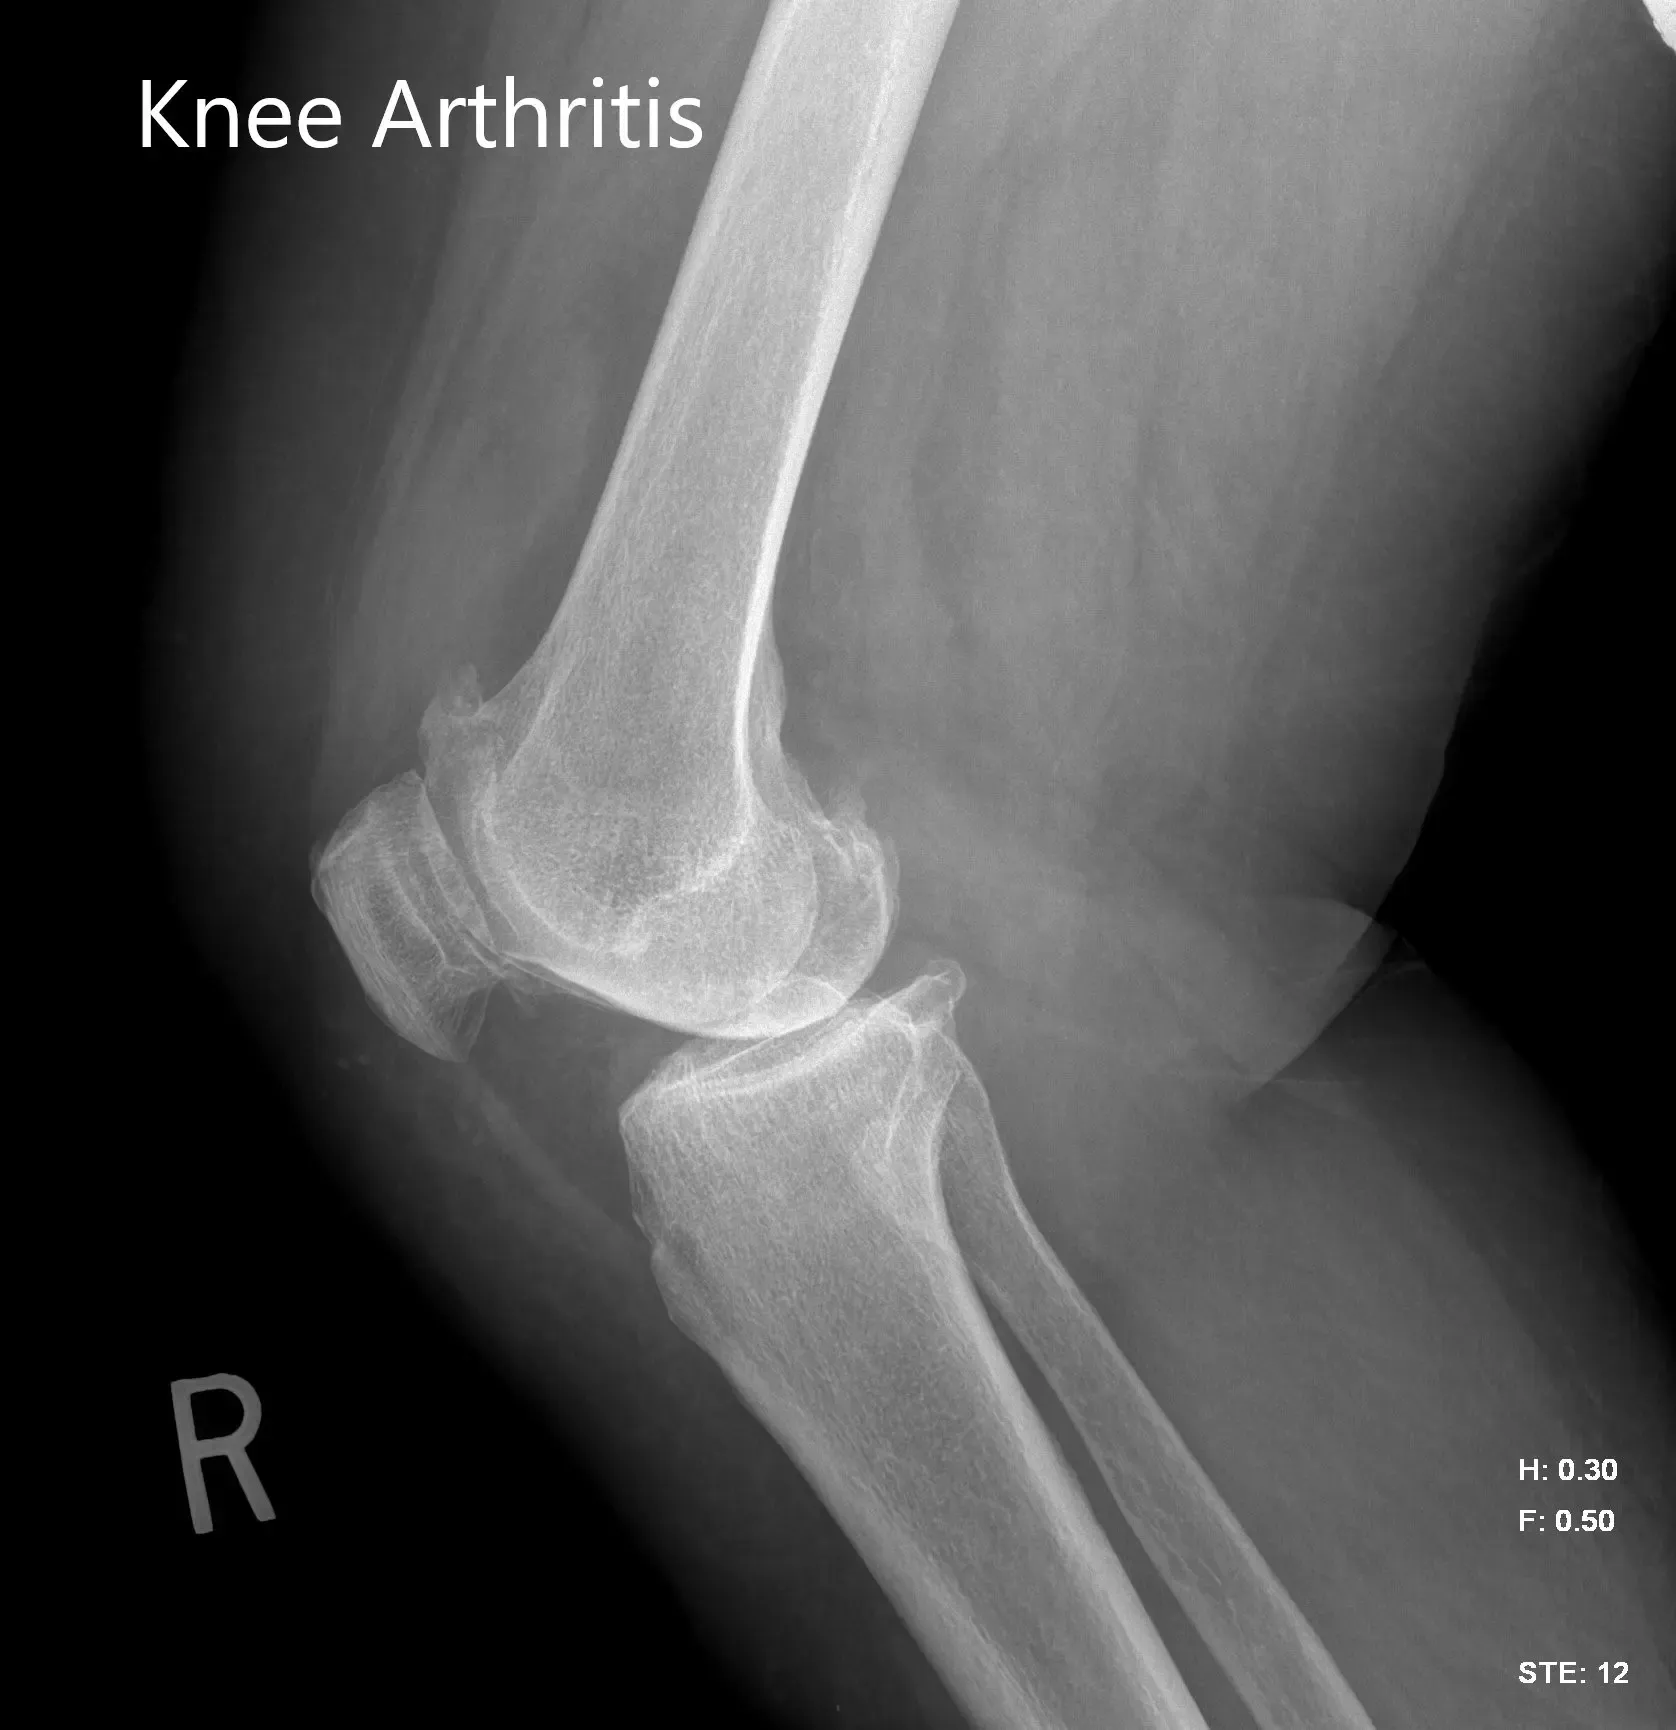

Imaging studies were obtained revealing tricompartmental osteoarthritis of the right knee with severe involvement of the medial compartment. Considering the patient’s condition and demands, he was deemed as a candidate for total knee replacement with custom implants. Other treatment options including nonsurgical methods were discussed in detail with him. He agreed for a custom right knee replacement.

Preoperative X-ray image of the right knee showing AP and lateral views